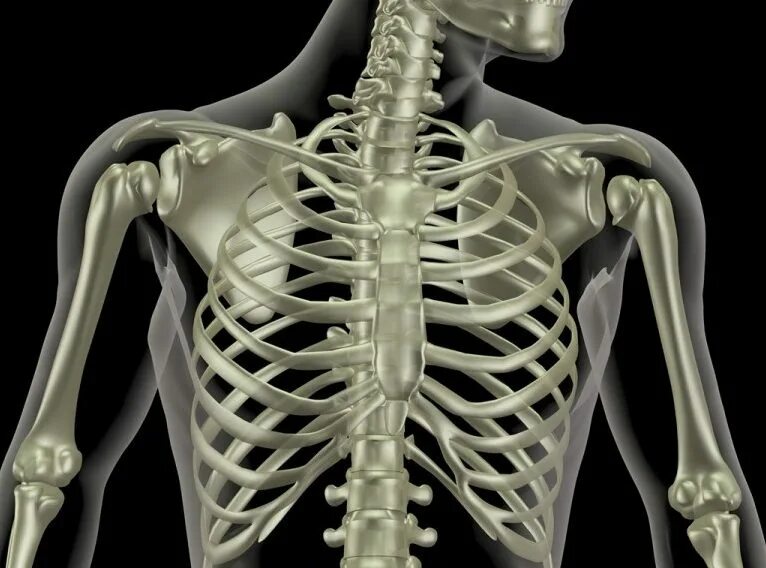

Хрустит ключица